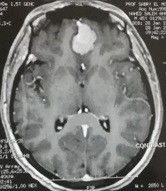

ورم بالفص الامامي بقاع الجمجمة

صورة فحص رنين مغناطيسي بالصبغة علي المخ لورم سحائي بالحجرة الامامية بقاع الجمجمة  قبل وبعد اجراء جراحة ميكروسكوبية  ناجحة لاستئصالة .